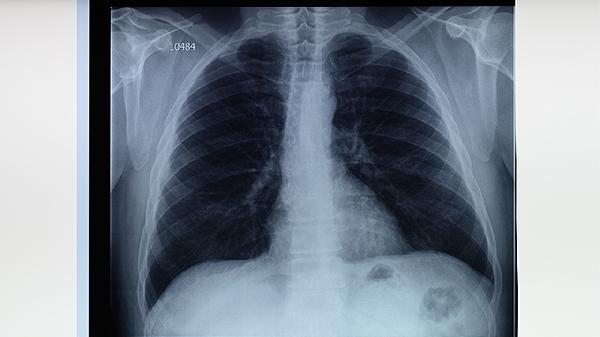

肺結核主要分為原發(fā)性肺結核、血行播散性肺結核、繼發(fā)性肺結核、結核性胸膜炎以及其他肺外結核五種類型。肺結核是由結核分枝桿菌感染引起的慢性傳染病,常見癥狀包括咳嗽、咳痰、低熱、盜汗等,需通過痰涂片、胸部影像學等檢查確診。

血行播散性肺結核是結核桿菌通過血液廣泛播散至肺部及其他器官的嚴重類型,可分為急性和慢性兩種。急性者起病急驟,表現(xiàn)為高熱、寒戰(zhàn)、呼吸困難;慢性者癥狀較隱匿,可能出現(xiàn)消瘦、持續(xù)低熱。影像學可見雙肺彌漫性粟粒樣結節(jié)。治療需聯(lián)合使用乙胺丁醇片、鏈霉素注射液等藥物,療程較長。

繼發(fā)性肺結核是成人最常見的類型,多由體內潛伏病灶復發(fā)或再次感染引起。病變多位于肺尖或鎖骨下區(qū),可形成空洞、纖維化或鈣化。典型癥狀包括咳嗽、咯血、胸痛等。治療需根據(jù)藥敏試驗選擇利福噴丁膠囊、對氨基水楊酸鈉顆粒等藥物組合,療程通常需6-9個月。